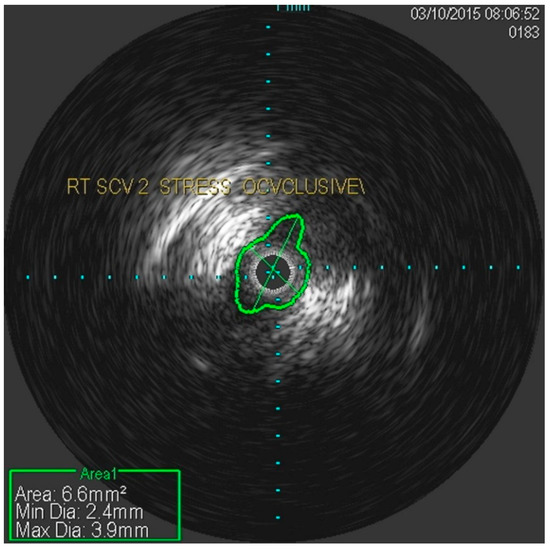

She underwent venography of the right arm venous system which revealed a 70–80% stenosis of the right subclavian vein in neutral position (Figure 1 and Figure 2). The vein was completely occluded in stress position. This was confirmed with intra-vascular ultrasound (IVUS). On IVUS measurements, the neutral position yielded a 74.4% stenosis while the stress position yielded 100% total occlusion (Figure 3 and Figure 4). It was noted that the contralateral vein appeared compressed in the costochondral space as well, though she was asymptomatic.

Figure 4.

Occlusion of the right subclavian vein in stress position as demonstrated by IVUS.